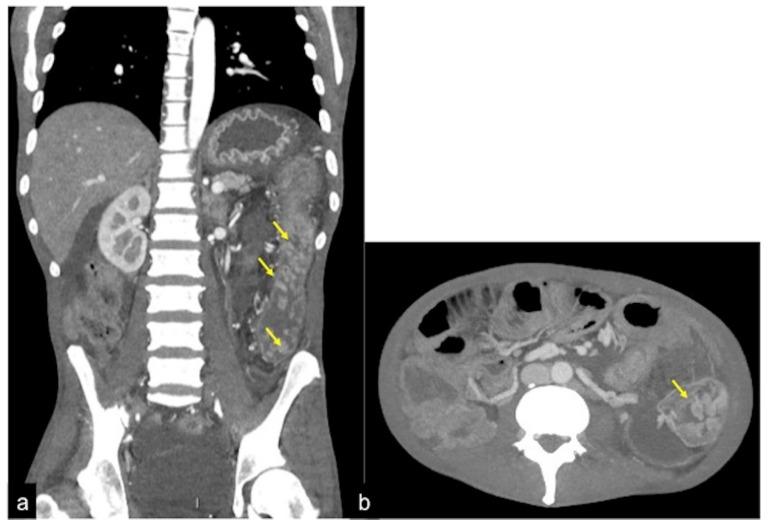

CT 血管造影在急性胃肠道出血中的作用:活跃和隐匿性发现的影像学描述。

The Role of CT-Angiography in the Acute Gastrointestinal Bleeding: A Pictorial Essay of Active and Obscure Findings.

Gastrointestinal bleeding is a potentially life-threatening abdominal emergency that remains a common cause of hospitalisation. Although 80-85% of cases of gastrointestinal bleeding resolve spontaneously, it can result in massive haemorrhage and death. The presentation of gastrointestinal bleeding can range from asymptomatic or mildly ill patients requiring only conservative treatments to severely ill patients requiring immediate intervention. Identifying the source of the bleeding can be difficult due to the wide range of potential causes, the length of the gastrointestinal tract and the intermittent nature of the bleeding. The diagnostic and therapeutic approach is fully dependent on the nature of the bleeding and the patient's haemodynamic status. Radiologists should be aware of the appropriate uses of computed tomography angiography and other imaging modalities in patients with acute gastrointestinal bleeding, as well as the semiotics of bleeding and diagnostic pitfalls in order to appropriately diagnose and manage these patients. The learning objective of this review is to illustrate the computed tomography angiography technique, including the potential role of dual-energy computed tomography angiography, also highlighting the tips and tricks to identify the most common and uncommon features of acute gastrointestinal bleeding and its obscure form.

胃肠道出血是一种潜在的危及生命的腹部急症,仍然是导致住院的常见原因。尽管 80-85%的胃肠道出血病例会自发缓解,但它可能导致大量出血和死亡。胃肠道出血的表现范围从无症状或轻度不适的患者仅需保守治疗到需要立即干预的严重疾病患者。由于潜在原因广泛、胃肠道长度长以及出血间歇性,确定出血部位可能很困难。诊断和治疗方法完全取决于出血的性质和患者的血流动力学状态。放射科医生应该了解在急性胃肠道出血患者中使用计算机断层血管造影和其他成像方式的适当用途,以及出血的征象和诊断陷阱,以便对这些患者进行适当的诊断和治疗。本次综述的学习目标是说明计算机断层血管造影技术,包括双能计算机断层血管造影的潜在作用,还强调了识别急性胃肠道出血及其隐匿形式的最常见和不常见特征的技巧和窍门。